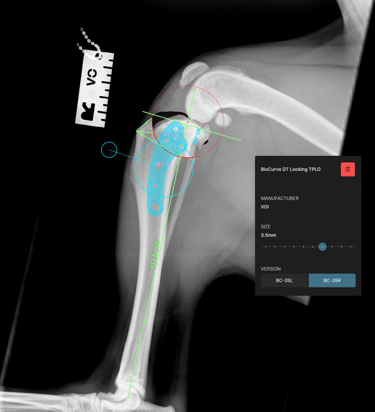

The surgical plan was developed using specialized veterinary orthopedic planning software, which allowed for precise measurements and implant selection, ensuring optimal execution of the surgical procedure (Figs. 3 and 4).

Preoperative measurements indicated a tibial plateau angle (TPA) of 25°. A TPLO saw blade size 24 was used, achieving a rotation of 8.3 mm. Pre-surgical measurements were: A = 11 mm, B = 13 mm, and C = 35 mm.

A 3.5 mm TPLO locking plate was placed with two compression screws. A 2 mm anti-rotational pin was left in situ, as it did not interfere with the placement of the proximal fragment screws.

Fig. 4